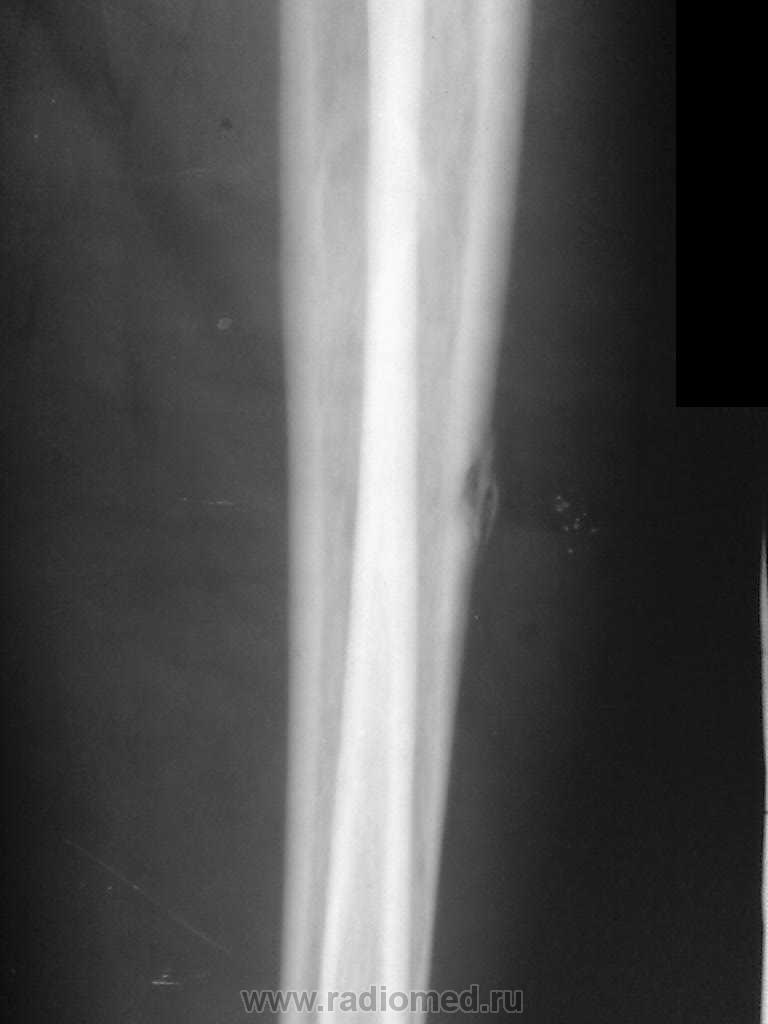

Еще предплечье, еще болгарка

ИзображениеИзображение